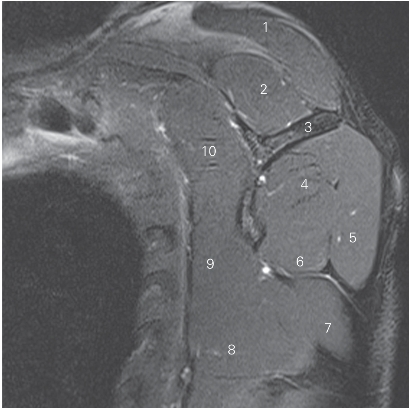

图4-22 经肩关节盂的矢状断层MR T2WI FS

1 锁骨 clavicle 2 冈上肌 supraspinatus

3 肩胛冈 spine of scapula 4 冈下肌 infraspinatus

5 小圆肌 teres minor 6 三角肌 deltoid

7 肱三头肌长头 long head of triceps brachii

8 大圆肌 teres major

9 腋窝血管神经束 axillary neurovascular bundle

10 关节盂 glenoid cavity 11 胸小肌 pectoralis minor

12 胸大肌 pectoralis major

13 喙突下滑囊 bursa mucosa of inferior coracoid pocess

14 喙突 coracoid prcess